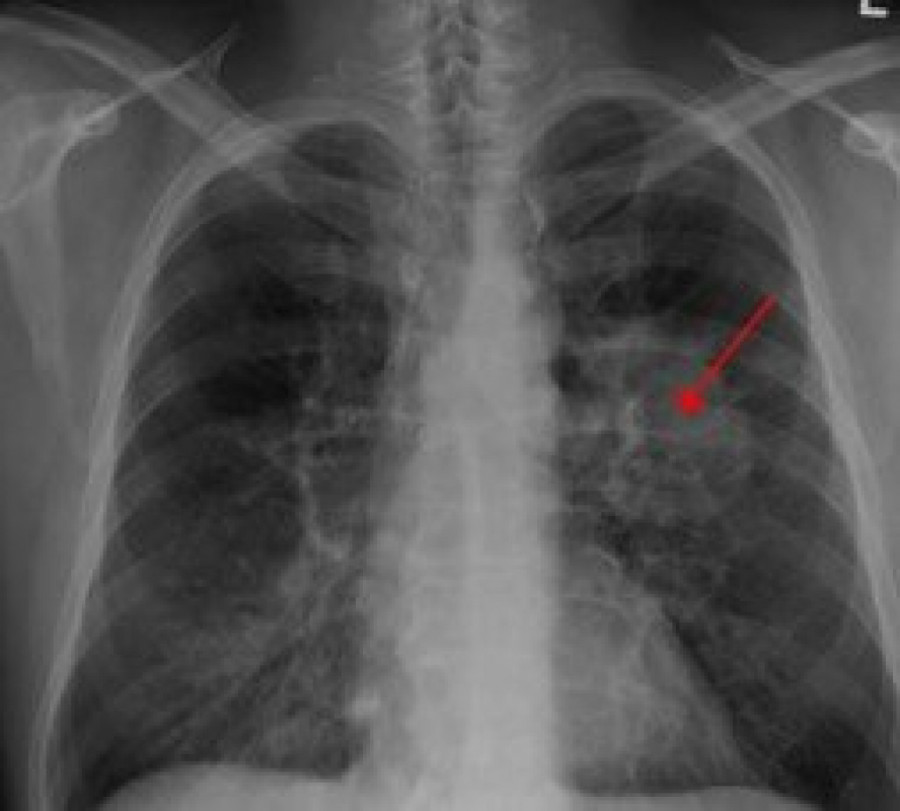

Dr Tatjana Radosavljević pulmolog u intervjuu je otkrila koji je simptom najspecifičniji za rak pluća. Ova teška bolest ne otkriva se lako, a zahteva punu pažnju kako pacijenata tako i doktora pri lečenju. Takođe, otkrila je i dva faktora rizika na koja posebno svako treba da obrati pažnju.

Rak pluća je rak koji počinje u plućima i može se proširiti na druge delove tela. Simptomi, izgled i lečenje zavise od stadijuma raka i koliko se proširio.

- Rak pluća je jedna od najtežih bolesti. Otkriva se teško jer su simptomi prikriveni. Postoji takozvana nema faza kada tumor raste, a pacijenti ne znaju. Prvi simptom, je krvarenje iz pluća, iskašljavanje iz pluća, to je karakteristično. Simptomi se ne razlikuju kod muškaraca i žena. Epidemiološki je pokazano da od raka pluća mogu oboleti i one žene koje nisu konzumirale cigarete - rekla je doktorka za naš portal.